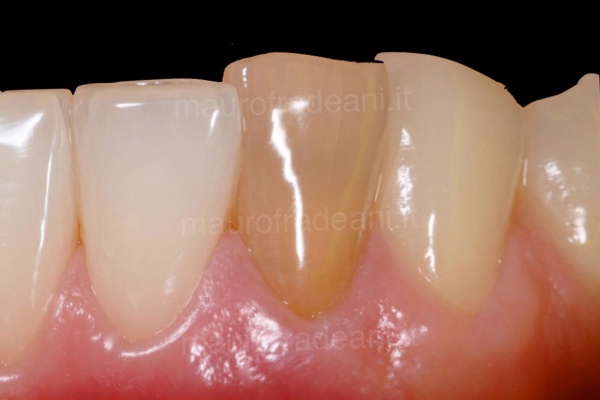

Ceramic veneers: severely worn dentition

1/5: Severe dental wear has significantly reduced the length of the central incisors of this young patient.

2/5: The front teeth before treatment involving ceramic veneers.

3/5: The 4 ceramic restorations, with a thickness of only a few tenths of a millimeter, are ready to be cemented.

4/5: Final picture of the 4 restorations, showing an excellent integration with the surrounding gingival tissues. The esthetic appearance is significantly improved thanks to the new contours, the new proportions and the dominance of the central incisors.

5/5: After 8 years, the restorations show an excellent functional, biological and esthetic integration.